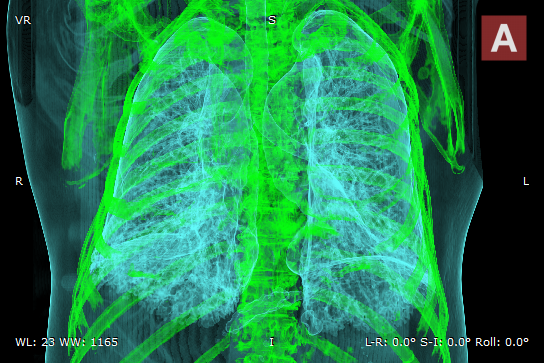

MIP B/W

MIP B/W Inverse